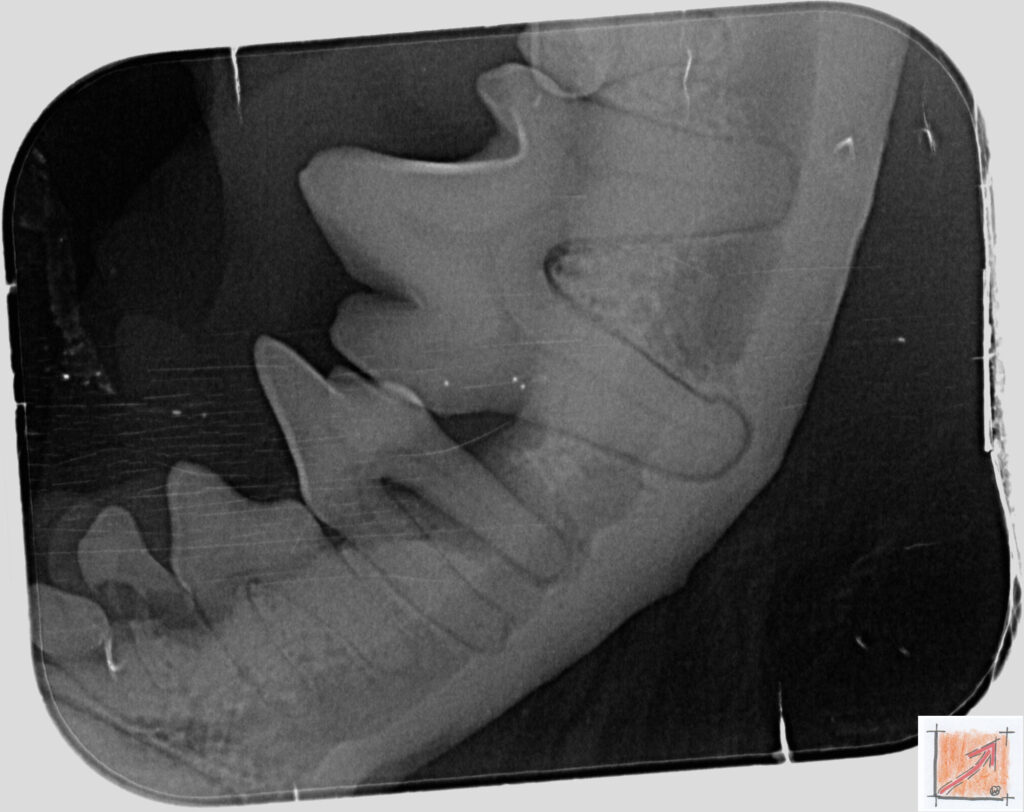

Röntgenbilder vom Thierrischen Orakel bei der Zahn-OP:

Warum Dentalröntgen beim Chihuahua lebenswichtig ist:

Ein Blick hinter die Kulissen von Chihuahua-Zähnen:

In dieser Galerie zeigen wir exklusive intraorale Röntgenaufnahmen einer Zahn-Operation beim Thierrischen Orakel als Chihuahua vom BauFachForum. Während oberflächlicher Zahnstein oft sichtbar ist, verbirgt sich die wahre Gefahr für das Herz meist unter dem Zahnfleischsaum.

Das digitale Dentalröntgen ist der Goldstandard in der modernen Tiermedizin, um parodontale Entzündungsherde und Wurzelabszesse sicher zu diagnostizieren. Für Chihuahuas wie dem Thierrischen Orakel, mit Mitralklappeninsuffizienz ist dieser diagnostische Schritt essenziell. Nur wenn versteckte Bakterienherde an der Zahnwurzel oder mit dem Fachbegriff Apikalabszesse erkannt und saniert werden, kann das Risiko einer bakteriellen Endokarditis oder einfach ausgedrückt einer Herzinnenhautentzündung minimiert werden.

Unsere Aufnahmen von Patienten dem Thierrischen Orakel verdeutlichen den Unterschied zwischen einer rein optischen Zahnreinigung und einer medizinisch fundierten Sanierung unter Röntgenkontrolle.

Chihuahua Mitralklappeninsuffizienz Trachealkollaps:

Wichtig ist im Vorfeld die Zahnhygiene des Chihuahuas. Die Bilder zeigen Dentale Röntgenbilder vom Thierrischen Orakel als Chihuahua-Hund während seiner Zahn-OP. Darstellung von Kieferknochen und Zahnwurzeln zur Diagnose von Parodontitis.

Zahnröntgenaufnahme bei Chihuahua Thierry:

Intraorales Dentalröntgen eines Chihuahuas:

Die Bilder zeigen Zähne und Wurzelstrukturen im Unterkiefer zur Planung einer Extraktion bei hochgradigem Zahnstein.